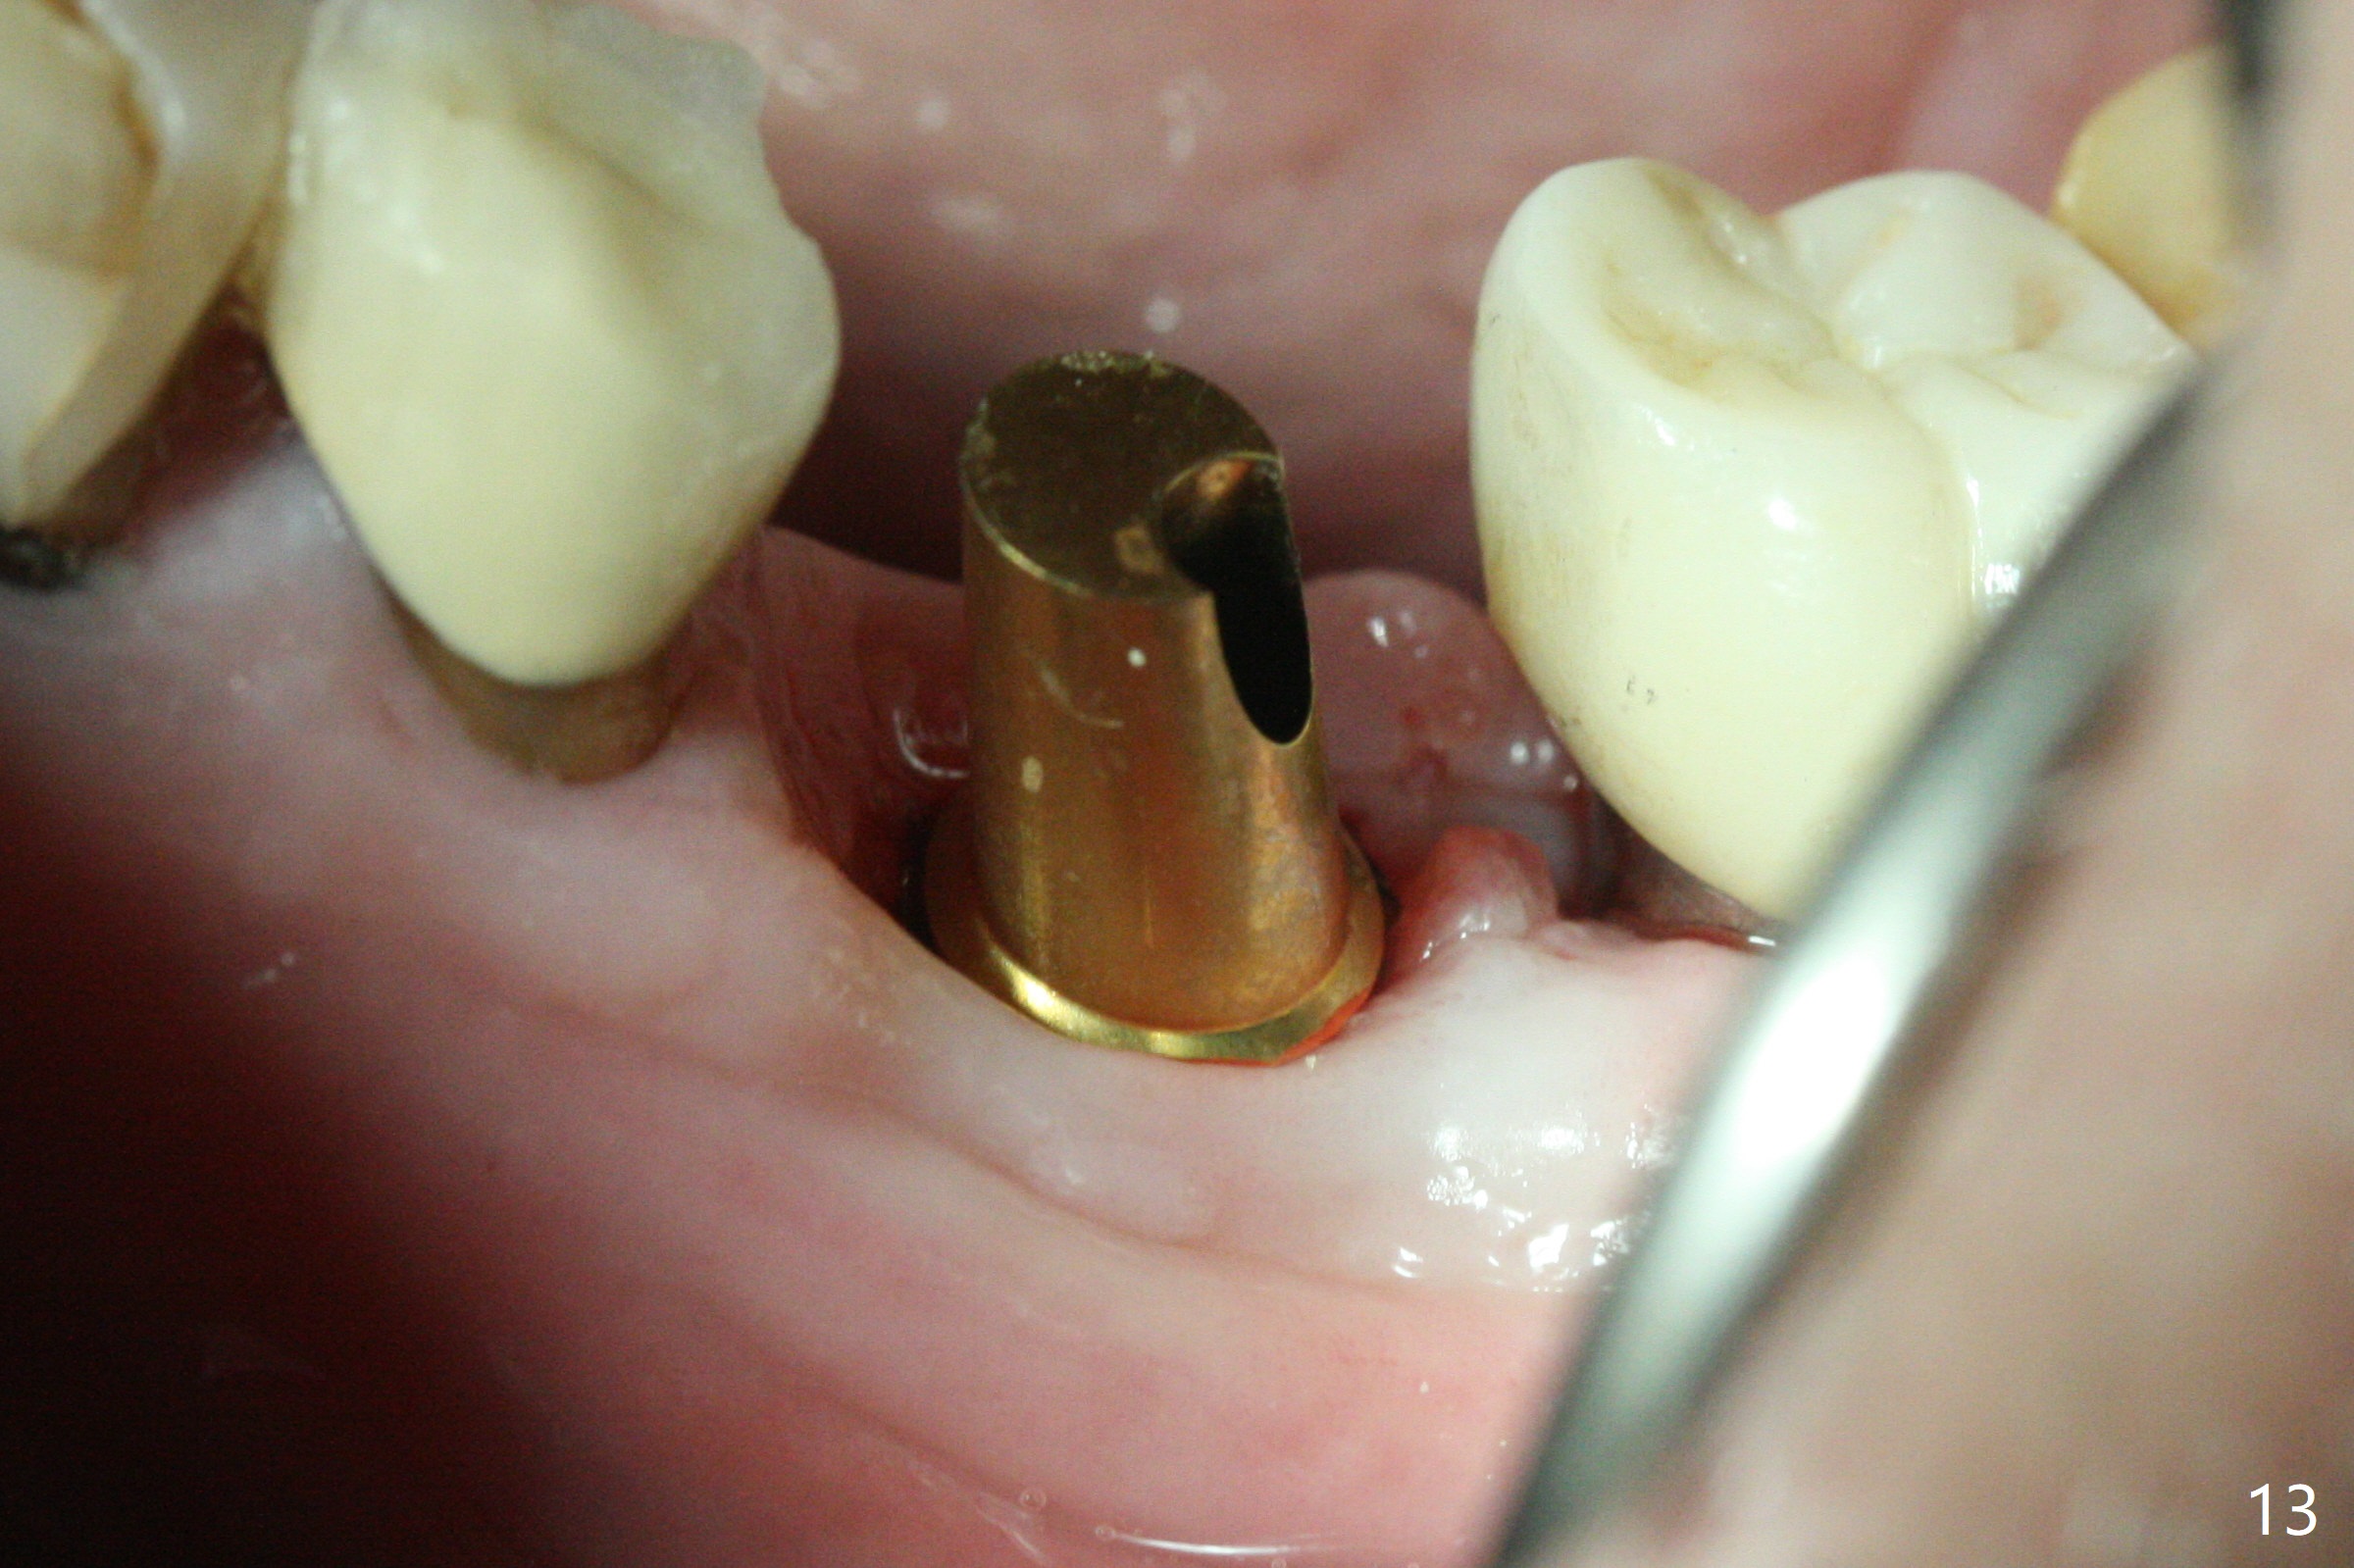

Extraction of the residual roots at #19 (Fig.1) is difficult, partially due to the hard one. The latter contributes to primary stability of 5x10 mm IS implant placed in the septum (Fig.2 (*),3). After change of cementation abutment (5.2x4.5(2) mm (short for provisional)) to hexed temporary abutment (5.2x8(2) mm), Collagen plug and Vera Graft are placed in the remaining mesial and distal socket (Fig.4 *). The last PA is taken when the temporary abutment (Fig.6 (<: hexed portion)) and provisional (P) are removed for modification. Before the abutment/provisional complex returns, a 2nd round of graft is placed (Fig.5 *). After the complex is seated, a 3rd round of graft is placed buccally (Fig.7). The temporary abutment is retightened 2 months postop (Fig.8). The implant appears to be osteointegrated 3.5 months postop (Fig.9). The gingiva looks healthy with (Fig.10) and without the provisional (Fig.11,12). It appears that there is no or minimal buccal plate loss. After insertion of a 5.7 x3 mm 15 degree (B-type) angled abutment (Fig.13) and height adjustment, impression is taken. The provisional is reseated after impression. The mesial bony defect seems to have been repaired nearly 8 months postop, 3 months post cementation (Fig.14 *). The bone density increases mesially 11 months post cementation (Fig.15).